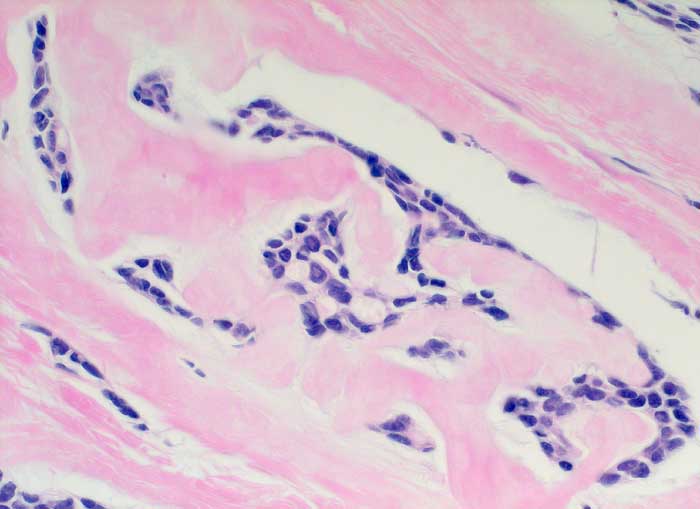

Adenoidzystisches Karzinom der Mamma

Adenoidzystische Karzinome machen lediglich 1% aller Mammakarzinome aus. Die Morphologie ist identisch mit dem gleichnamigen Tumor der Speicheldrüsen. Die Zellen des adenoidzystischen Karzinoms bilden kohäsive Verbände und Drüsen oder mikrozystische Strukturen. Die Tumorzellen sind klein und monomorph, die Kern-Zytoplasmarelation ist hoch. Die Kerne sind dunkel, rund bis oval oder angulär und enthalten bisweilen einen kleinen Nukleolus. Azelluläre hyaline Körperchen aus mucoidem Material, welche die Hohlräume der intakt aspirierten kribriformen Strukturen ausfüllen, sind besonders typisch. Das mucoide Material kann auch verzweigte oder fingerartige abgerundete Strukturen ausbilden.